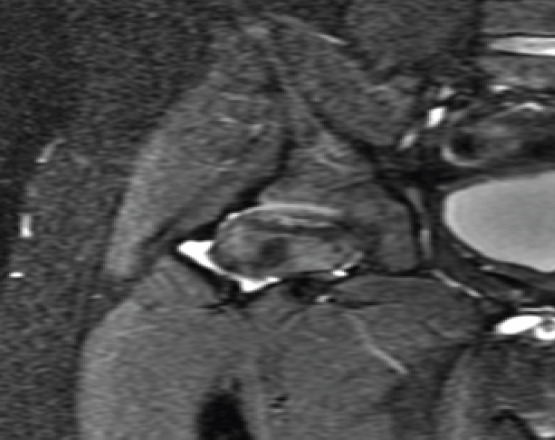

Case report: In this report, we present the case of an 8-year-old Hispanic male who presented with bilateral hip pain unresponsive to conservative treatment and initially managed with the presumptive diagnosis of LCP disease. Due to his persistent hip pain and no improvement on follow-up X-rays and magnetic resonance imaging (MRI), the patient was referred to our hip preservation clinic for further work-up and management recommendations. MRI revealed bilateral OCD lesions of the femoral head secondary to developmental hip dysplasia. The patient underwent bilateral triple PAO for correction of the patient's bilateral hip dysplasia, which resulted in the proper resolution of the femoral head lesions on imaging and eventually resolved the patient's hip pain.